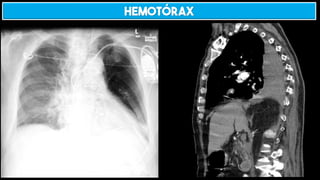

HEMOTÓRAX